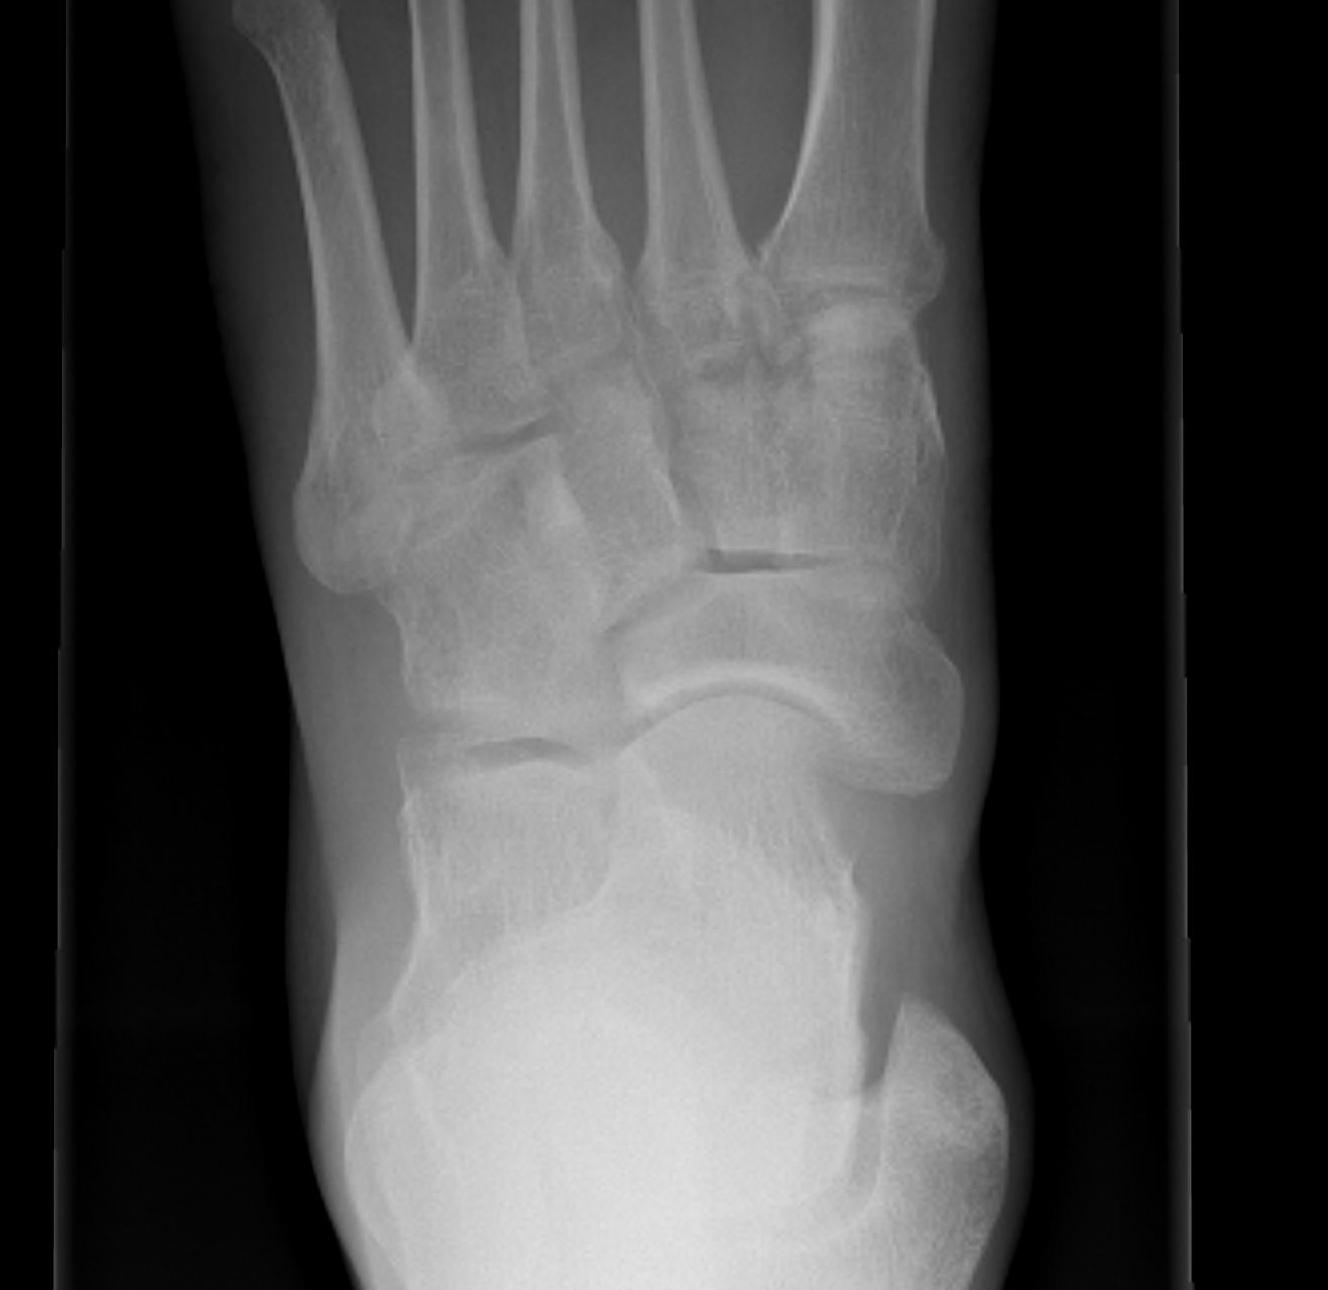

Classification

| Type I | Type II | Type III |

|---|---|---|

|

Small ossicle proximal to insertion In the Tibialis posterior tendon |

Triangular ossicle Connected to navicular via syndesmosis May fracture with injury |

Enlarged medial navicular Cornuate navicular Likely that Type II accessory navicular has fused |